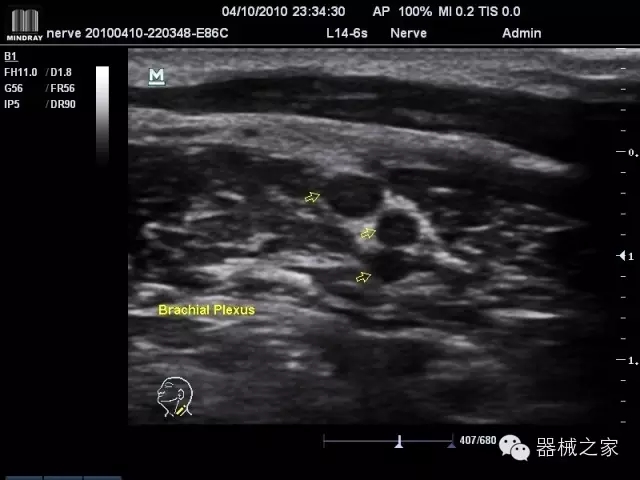

經(jīng)典產(chǎn)品:M7(星鉆)

臨床圖片賞析

產(chǎn)品特點(diǎn)

·優(yōu)秀的圖像效果、強(qiáng)大的功能體驗(yàn)、豐富的探頭選擇、合理的便攜式設(shè)計(jì),全中文顯示及病人管理界面,使得M7在任何場(chǎng)合、任何時(shí)候都能快速響應(yīng)更好的心血管、腹部、婦產(chǎn)、小器官等常規(guī)超聲檢查以及肌骨、神經(jīng)、顱腦、術(shù)中等新興領(lǐng)域的使用需求;